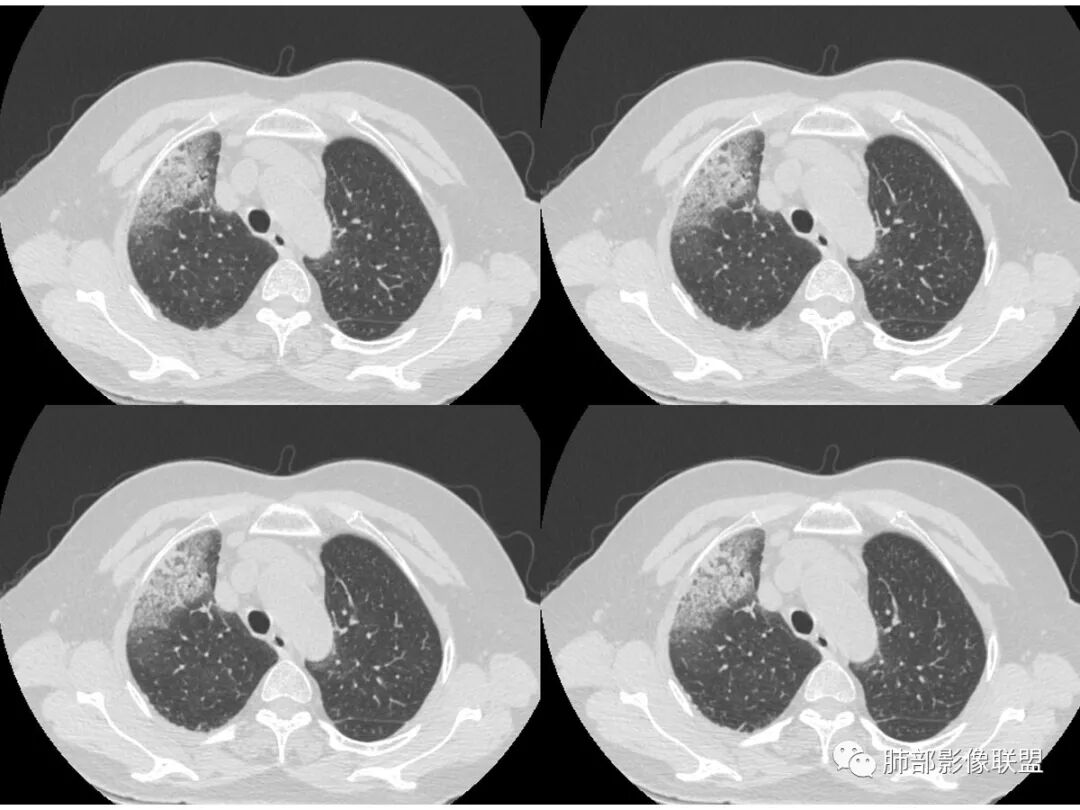

胸CT:右肺上叶实变内可见支气管充气征,近端支气管狭窄,远端扩张,周围可见毛玻璃影,右肺中叶支气管闭塞,并可见气道壁钙化,右肺中叶体积缩小,实变内可见空洞,并可见气液平面,空洞周围可见毛玻璃样影,右肺下叶支气管开口狭窄,右肺门淋巴结肿大。纵隔窗可见病灶与壁层胸膜间隙增宽,考虑良性病变-----感染性病变------TB?

病史老年女,白痰;影像实变,ggo多数边界清,病灶下缘部分不清,枯树枝,支气管近端阻塞、僵硬,病灶跨叶;病灶内空洞,有液平;间质增厚有结节感;肺炎型肺癌大于干酪性肺炎。

老年女性,慢性病程,咳嗽伴白色粘液痰,无发热腹痛,糖尿病,白细胞及C反应蛋白不高,血沉快,铁蛋白高。胸部CT,右肺上叶大片状实变伴磨玻璃密度影,边界不清,边缘局部膨隆,叶裂弧形下坠,实变影宽基底与胸膜相贴;右肺下叶前基底段见类似病灶;右肺中叶不张并空洞形成,空洞内见气液平面;综合考虑右肺上叶及下叶肺炎型肺癌,右肺中叶结核。

老年女性,病史1月,右肺上中叶大片状影,跨叶,上叶为主,磨玻璃为主,边界模糊,部分实变,内见空洞影和液气平面,壁光滑,支气管开口狭窄,局部有扩张,右肺门淋巴结钙化,首先考虑感染性病变,结核可能,鉴别粘液腺癌。

老年女性,亚急性起病,右肺上中叶大片状影,跨叶,上叶为主,磨玻璃为主,边界模糊,部分实变,内见空洞影和液气平面,壁光滑,洞内可见结节形成,局部有扩张,首先考虑感染性病变,结核可能;洞内可见结节样病灶,鉴别合并曲霉、肿瘤。

患者老年女性,亚急性起病,胸部CT:右肺上叶大片实变,可内见坏死性空洞,可见mGGO,GGO边缘清晰,局部彭隆,内见支气管充气征,可惜没增强,粘液腺癌要考虑,但病灶明显是内朝外不支持,综合考虑结核,建议查痰找抗酸杆菌、气管镜

老年女性,咳白色粘液痰,右肺跨叶大片高密度影,密度不均匀,其内见支气管枯树征,有空洞,边缘部分清楚,叶间裂有下坠膨隆感。考虑粘液腺癌,鉴别干酪性肺炎

实变区像支气管爬行征?空洞区也有钙化和边界清楚模玻璃影

以前老师们也讲过边界清楚的模玻璃影及反晕征注意TB

3.熊老师告诉我们:肺结核可以有磨玻璃,这个我以前一直不知道,右肺门淋巴结有钙化,病灶内纵膈窗隐约细细点状钙化,所以结核磨玻璃可以,